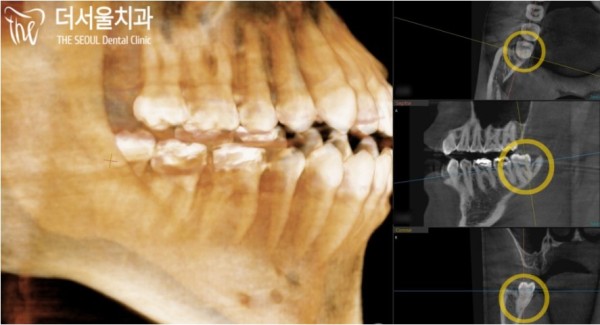

CT촬영을 통해 자세히 보니, 신경관과 사랑니 사이에

약간의 거리가 있는것이 보입니다.

이러면 가능하죠. 약 2분만에 환자분의 사랑니를 발치할 수 있었답니다.

CT scan shows that between the neural tube and the wisdom tooth

I can see that there is a little distance.

It's possible. She was able to extract her wisdom tooth in about two minutes.